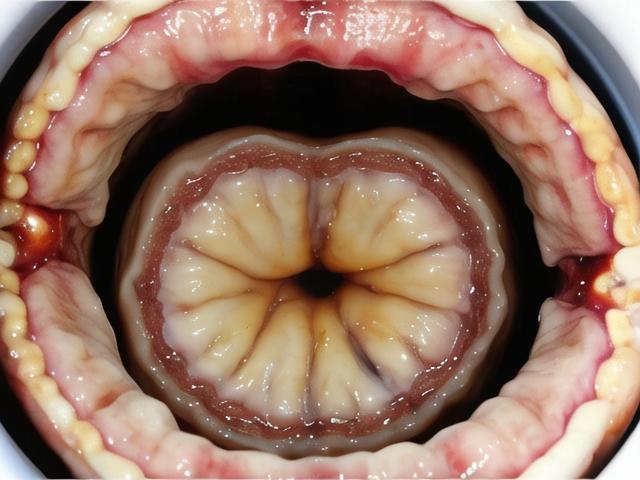

贲门是胃与食管交界处的一个生理性狭窄部位,主要功能是防止胃内容物反流至食管,当贲门关闭不严时,胃酸和食物容易反流至食管,导致一系列不适症状,严重时甚至会引起食管炎、食管溃疡等疾病,本文将详细介绍贲门关闭不严的治疗 *** 及日常护理要点。